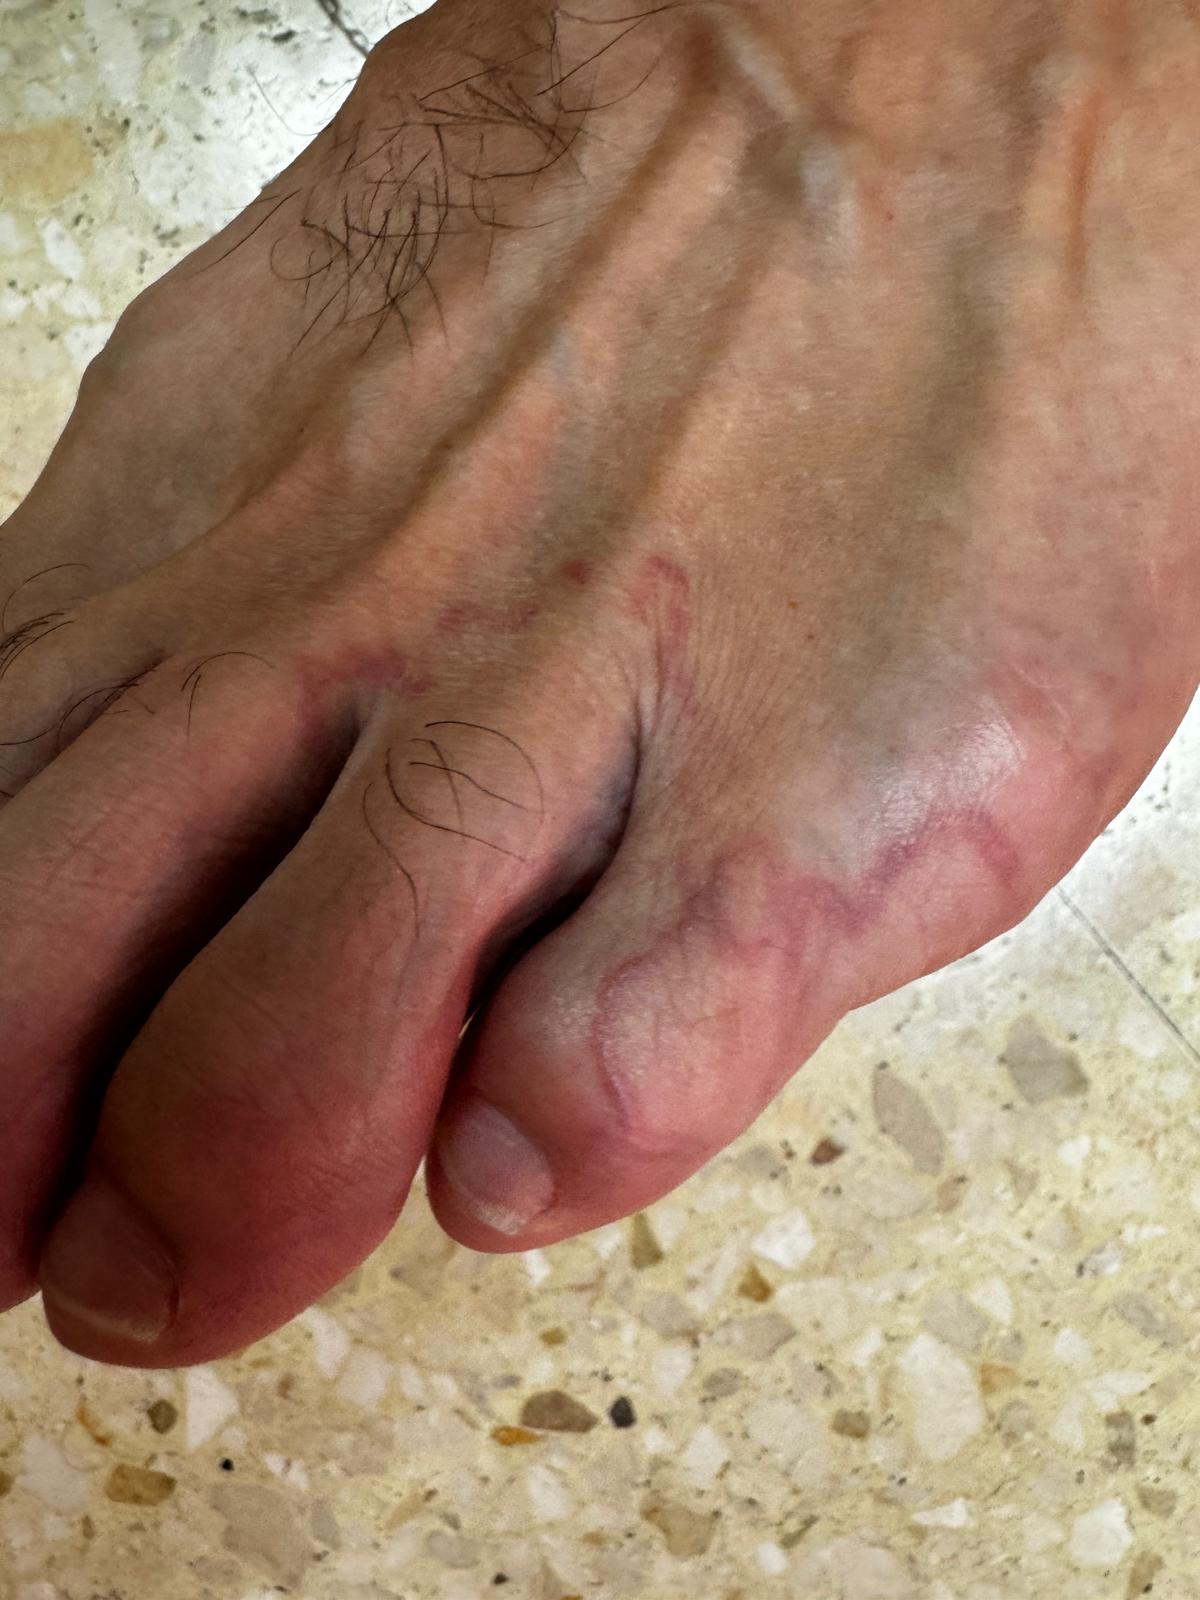

Anamnesis: Hombre de 37 años sin antecedentes personales de interés, acude al servicio de urgencias por intenso picor en pie izquierdo de tres días de evolución. El paciente refiere presentar una lesión cutánea que inicia tras su llegada de América del Sur hace siete días y se ha ido extendiendo progresivamente en la región dorsal de dicho pie. Niega fiebre. No disnea ni alteraciones gastrointestinales. No otros familiares afectos. No otros signos o síntomas de alarma en el momento actual.

Exploración física: En región dorsal del quinto dedo del pie izquierdo presenta lesiones pápulo-eritematosas con superficie excoriada y costrosa, aspecto filiforme y trayecto serpiginoso con extensión al cuarto dedo.

Juicio clínico: Larva migrans cutánea.

Evolución: Paciente con favorable evolución clínica, ausencia de progresión parasitaria con disminución de pápulas y pérdida de intensidad de la lesión eritematosa. En analítica se aprecia eosinofilia sin afectación hepática. Radiografía de tórax sin hallazgos patológicos.